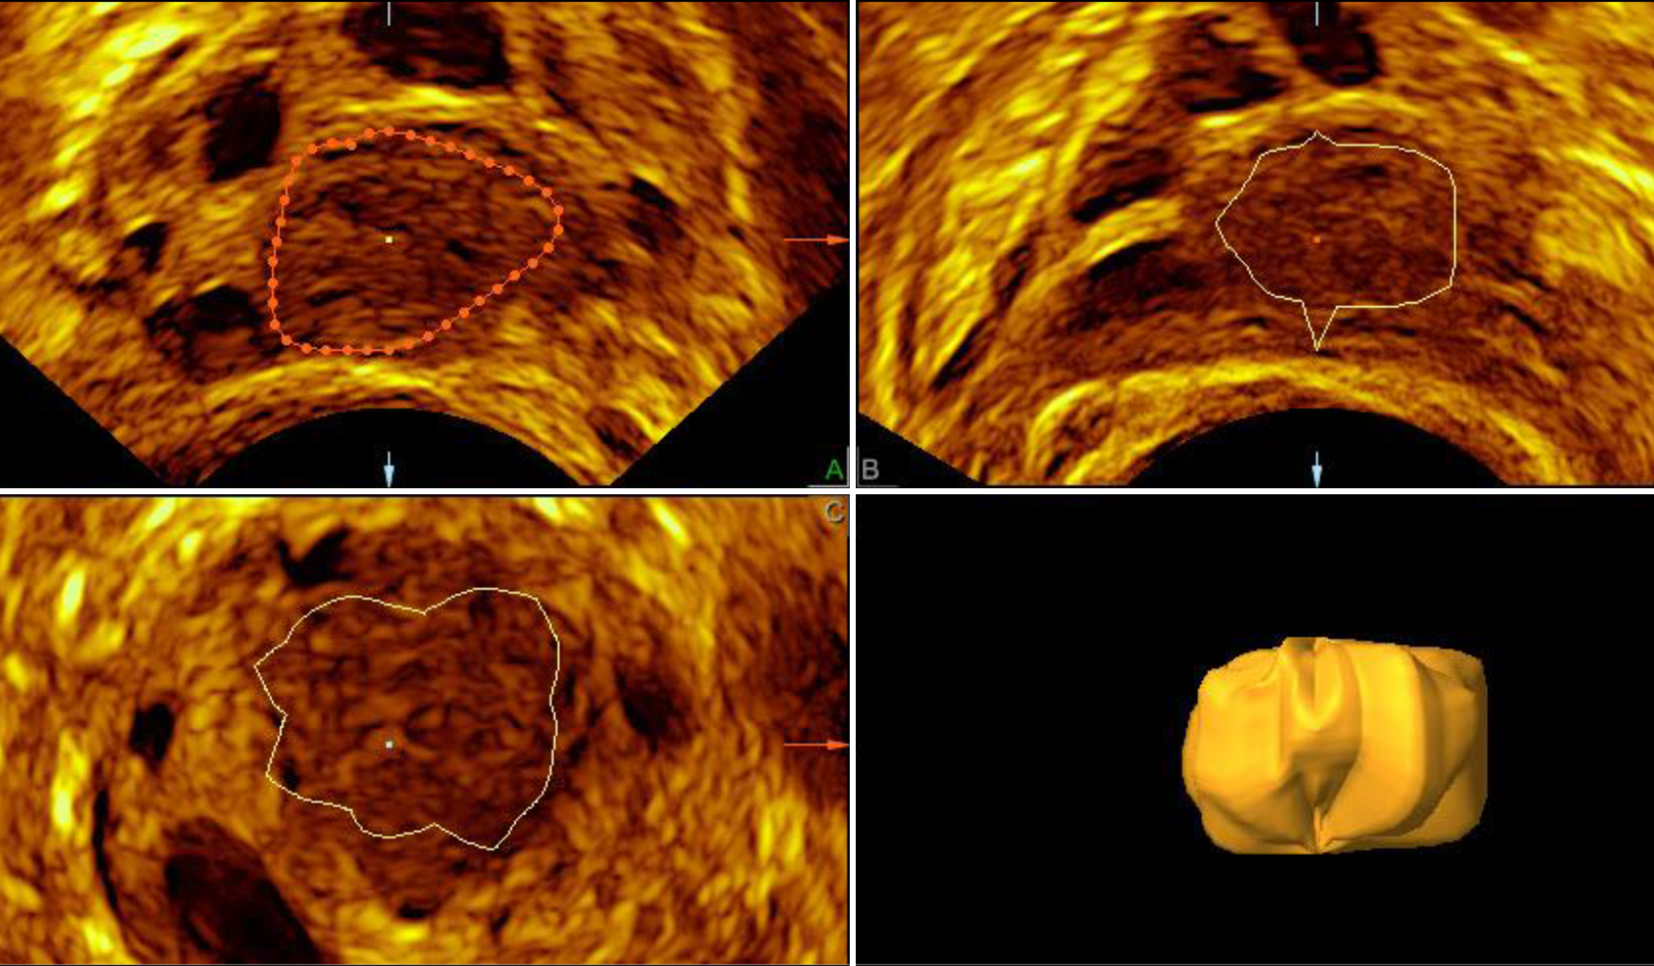

Abb. 7

Die manuelle 3‑D-Darstellung des Corpus luteum mit dem integrierten Grafikprogramm kann nur offline nach der eigentlichen Untersuchung durchgeführt werden. Der diagnostische Mehrwert ist überschaubar

Der 3‑D-Ultraschall kann bei der Darstellung des Corpus luteum diagnostisch durchaus hilfreich sein: Die Tomographic-ultrasound-Methode ermöglicht es, in vorher gewählten Abständen bis zu 9 Schnitte des Ovars nebeneinander am Bildschirm darzustellen und sich ein Bild von dem CL innerhalb des Ovars zu machen (Abb. 5). Die Sono-AVC™-Methode hat ihren idealen Einsatz in der ersten Zyklushälfte. Bei einem deutlich flüssigkeitsgefüllten Corpus luteum kann dieses als irregulär umrandete Struktur dargestellt werden (Abb. 6). Die manuelle 3‑D-Darstellung des Corpus luteum mit dem integrierten Grafikprogramm kann nur offline nach der eigentlichen Untersuchung durchgeführt werden. Der diagnostische Mehrwert ist begrenzt (Abb. 7; [2]).